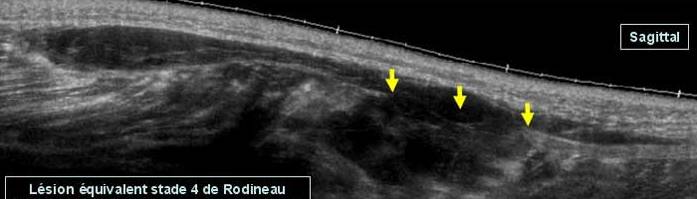

Echivalentul stadiului IV al lui Rodineau se caracterizeaza prin existenta unei rupturi sau unei dezinsertii musculo-aponevrotice complete cu,cel mai frecvent fascicol muscular retractat flotant intr-o cavitate hematica

Echivalentul stadiului IV al lui Rodineau se caracterizeaza prin existenta unei rupturi sau unei dezinsertii musculo-aponevrotice complete cu,cel mai frecvent fascicol muscular retractat flotant intr-o cavitate hematica Exista in aceste echivalente ale stadiului IV un caz particular, reprezentat de o ruptura osteotendinoasa (traumatismul spinei iliace antero-inferioare in leziunile dreptului femural la fotbalisti de exemplu

Stadiul IV Rodineau – ruptura la jonctiune mio tendinoasa

Muschi retractat flotant in colectie hematica